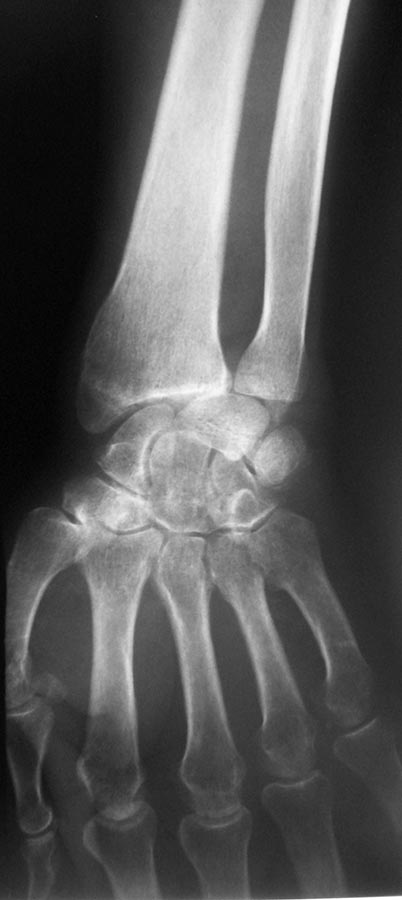

[Ortho] Застарелый вывих полулунной кости

Извиняюсь, вот от 20.02.2016 снимки.